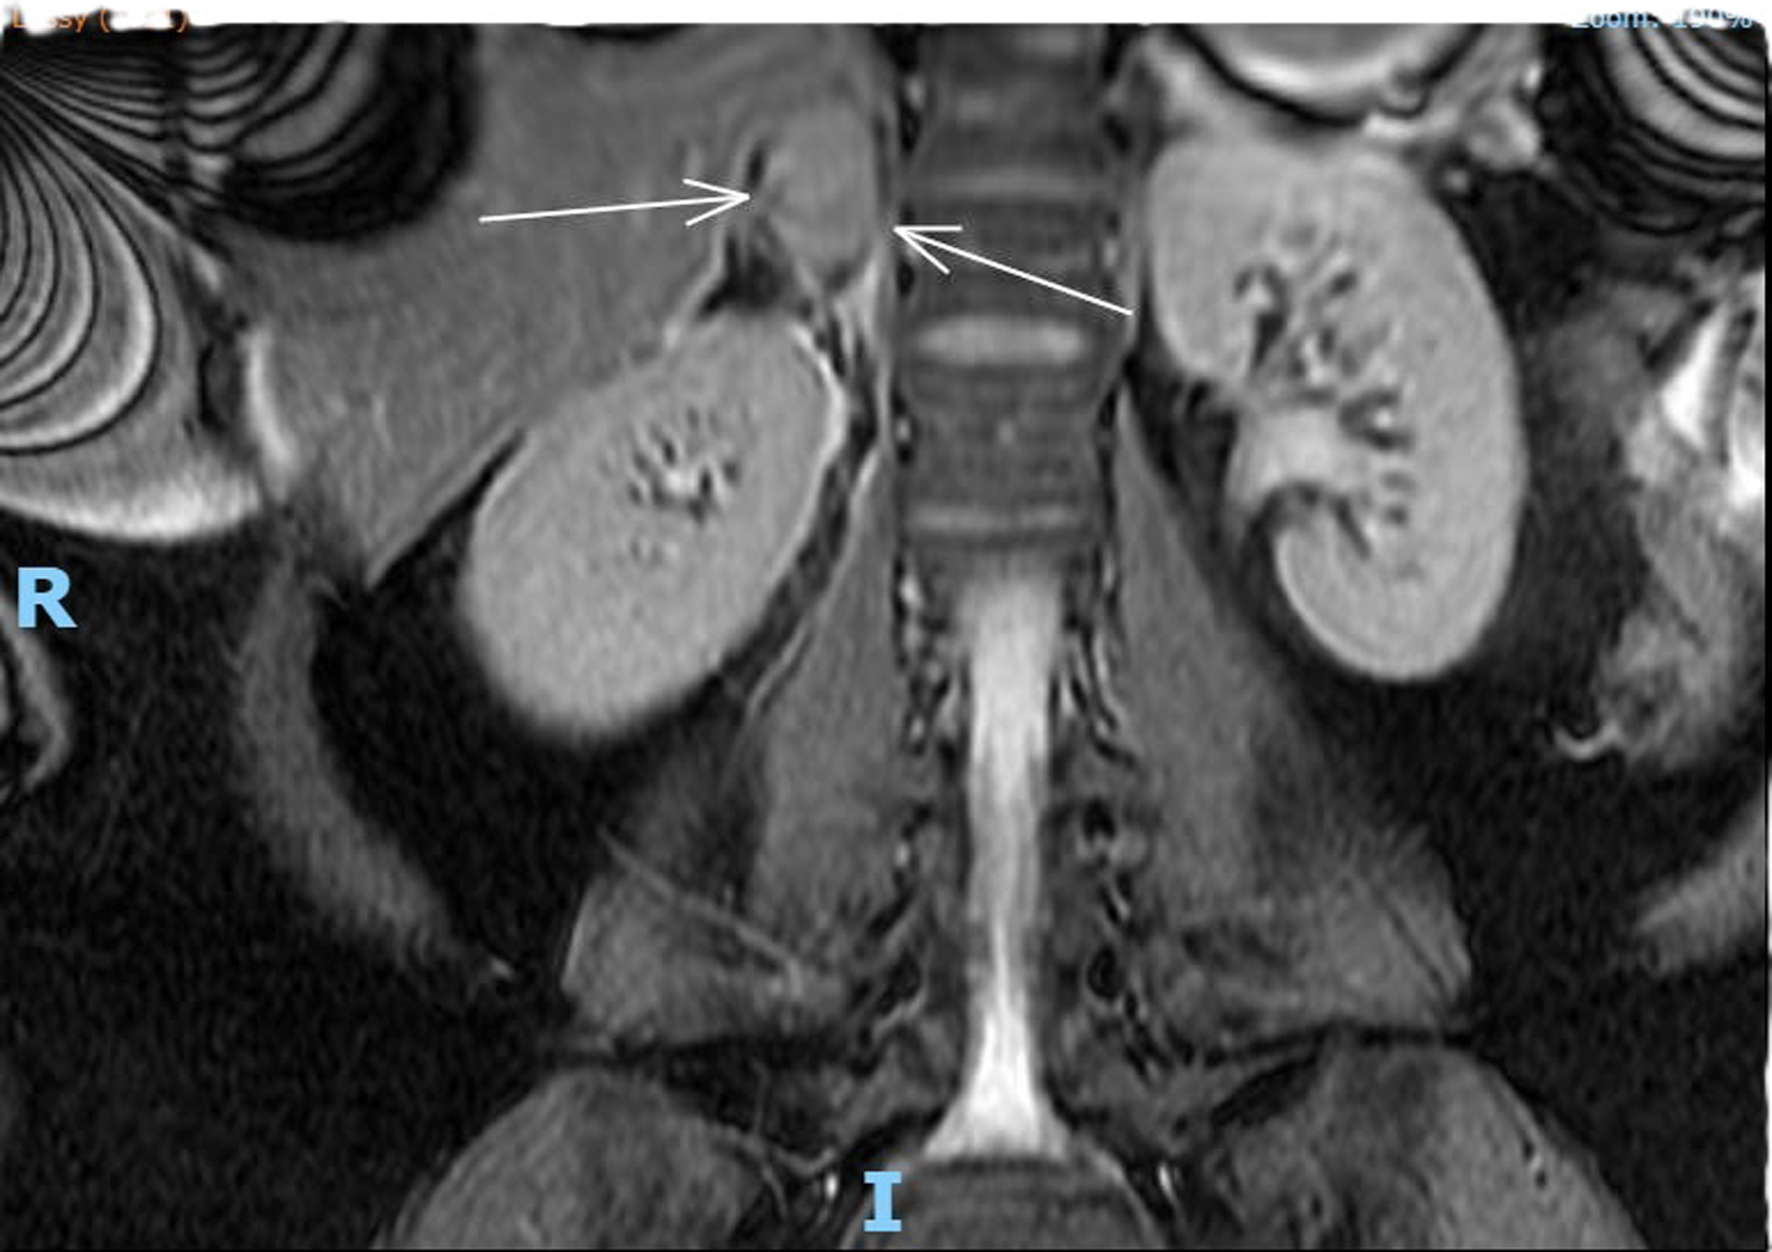

Complete full blood count, coagulation profile, liver function test, renal function test, and amylase were all within normal limits, with a total hemoglobin concentration of 122 g/dL, total leucocyte count of 9,600 mL, normal platelet count, C-reactive protein concentration of 6 mg/L, bile acid concentration of 1.8 µmol/L, creatinine concentration of 46 µmol/L, urea concentration of 1.9 mmol/L, and potassium level indeterminate because of hemolyzed specimen. Urine analysis was negative. Renal ultrasound revealed no evidence of hydronephrosis, mass, or calculi. An obstetric ultrasound performed 1 week prior revealed a live fetus with a normal anterior placenta and appropriate fetal growth with a normal liquor volume and umbilical artery Doppler. Abdominal ultrasound revealed a normal appearance of the gallbladder, no evidence of gallstones, a normal caliber of the common bile duct, and no focal abnormality or ascitic fluid identified with an obscured appendix. The patient was admitted and continued to experience persistent right flank pain with three episodes of vomiting and nausea. She experienced generalized fatigue and malaise 3 days post admission. Intravenous fluids and oral opioids were used to control pain. General surgery colleagues were consulted to rule out surgical causes of acute abdomen and concerns for possible related complications. On review of her investigations, there was a significant decrease in the hemoglobin level to 88 g/dL, a new increase in potassium to 9.6 mmol/L, chloride 117 mmol/L, and a significant steep increase in C-reactive protein levels of 101 and 233 mg/L. An MRI scan of the abdomen (Fig. 1) revealed coronal plane, T2-weighted sequence demonstrating an area of heterogeneous high T2 signal density. An arrow points to enlarged adrenal gland consistent with adrenal hemorrhage. MRI transverse plan (Fig. 2) revealed T2-weighted sequence demonstrating a 44 × 54 × 25 mm lesion centered in right adrenal gland with heterogeneous T2 signal compatible with spontaneous/acute adrenal hemorrhage. A trace amount of fluid surrounding the adrenal gland and right kidney is consistent with SAH. Transverse plane (Fig. 3) high T2 density signals showed enlarged adrenal gland.

Figure 1. MRI coronal plane, T2-weighted sequence demonstrating an area of heterogeneous high T2 signal density. An arrow points to enlarged adrenal gland consistent with adrenal hemorrhage.